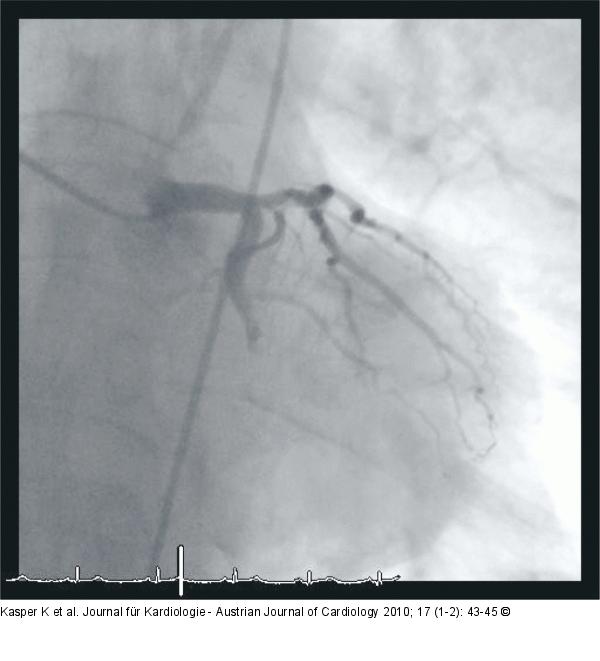

Abbildung 1: Ramus circumflexus

Thrombisch verschlossener Ramus circumflexus |